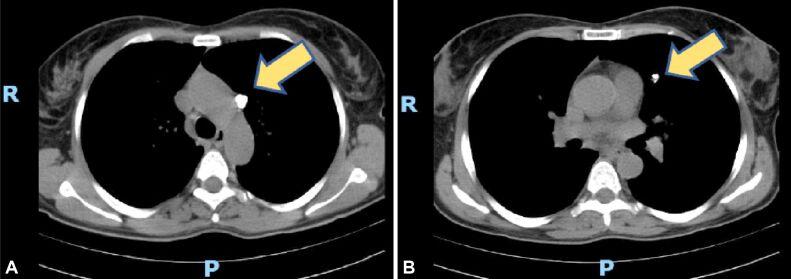

The most challenging cases encountered during the recent years were those of lung hamartoma associated with eosinophilic pneumonia because of the multicentricity of the disease and the suspicion for metastasis in the clinical setting, pulmonary aspergillosis that presented as a cystic lesion with a 9 mm mural nodule, actinomycosis discovered as firm nodule showing aspects of false pleural invasion, cryptococcosis - a hilar mass for which a pneumectomy was prepared, pulmonary parasitosis that presented as a nodule with irregular borders, causing pleural retraction, one case of inflammatory myofibroblastic tumor of the lung, one case of tumorlet type neuroendocrine lesion in a patient with history of melanoma and renal oncocytoma, admitted under the suspicion of lung metastasis.

近年来遇到的最具挑战性的病例是肺错构瘤伴嗜酸性肺炎,因为疾病的多中心性和临床环境中对转移的怀疑,表现为囊性病变伴 9 毫米壁结节的肺曲霉病,表现为假性胸膜侵犯特征的坚实结节的放线菌病,准备进行肺切除术的隐球菌病 - 肺门肿块,表现为不规则边界结节导致胸膜回缩的肺寄生虫病,一例肺部炎性肌纤维母细胞瘤,一例黑色素瘤和肾嗜酸细胞瘤病史患者的肿瘤样神经内分泌病变,怀疑为肺癌转移而入院。